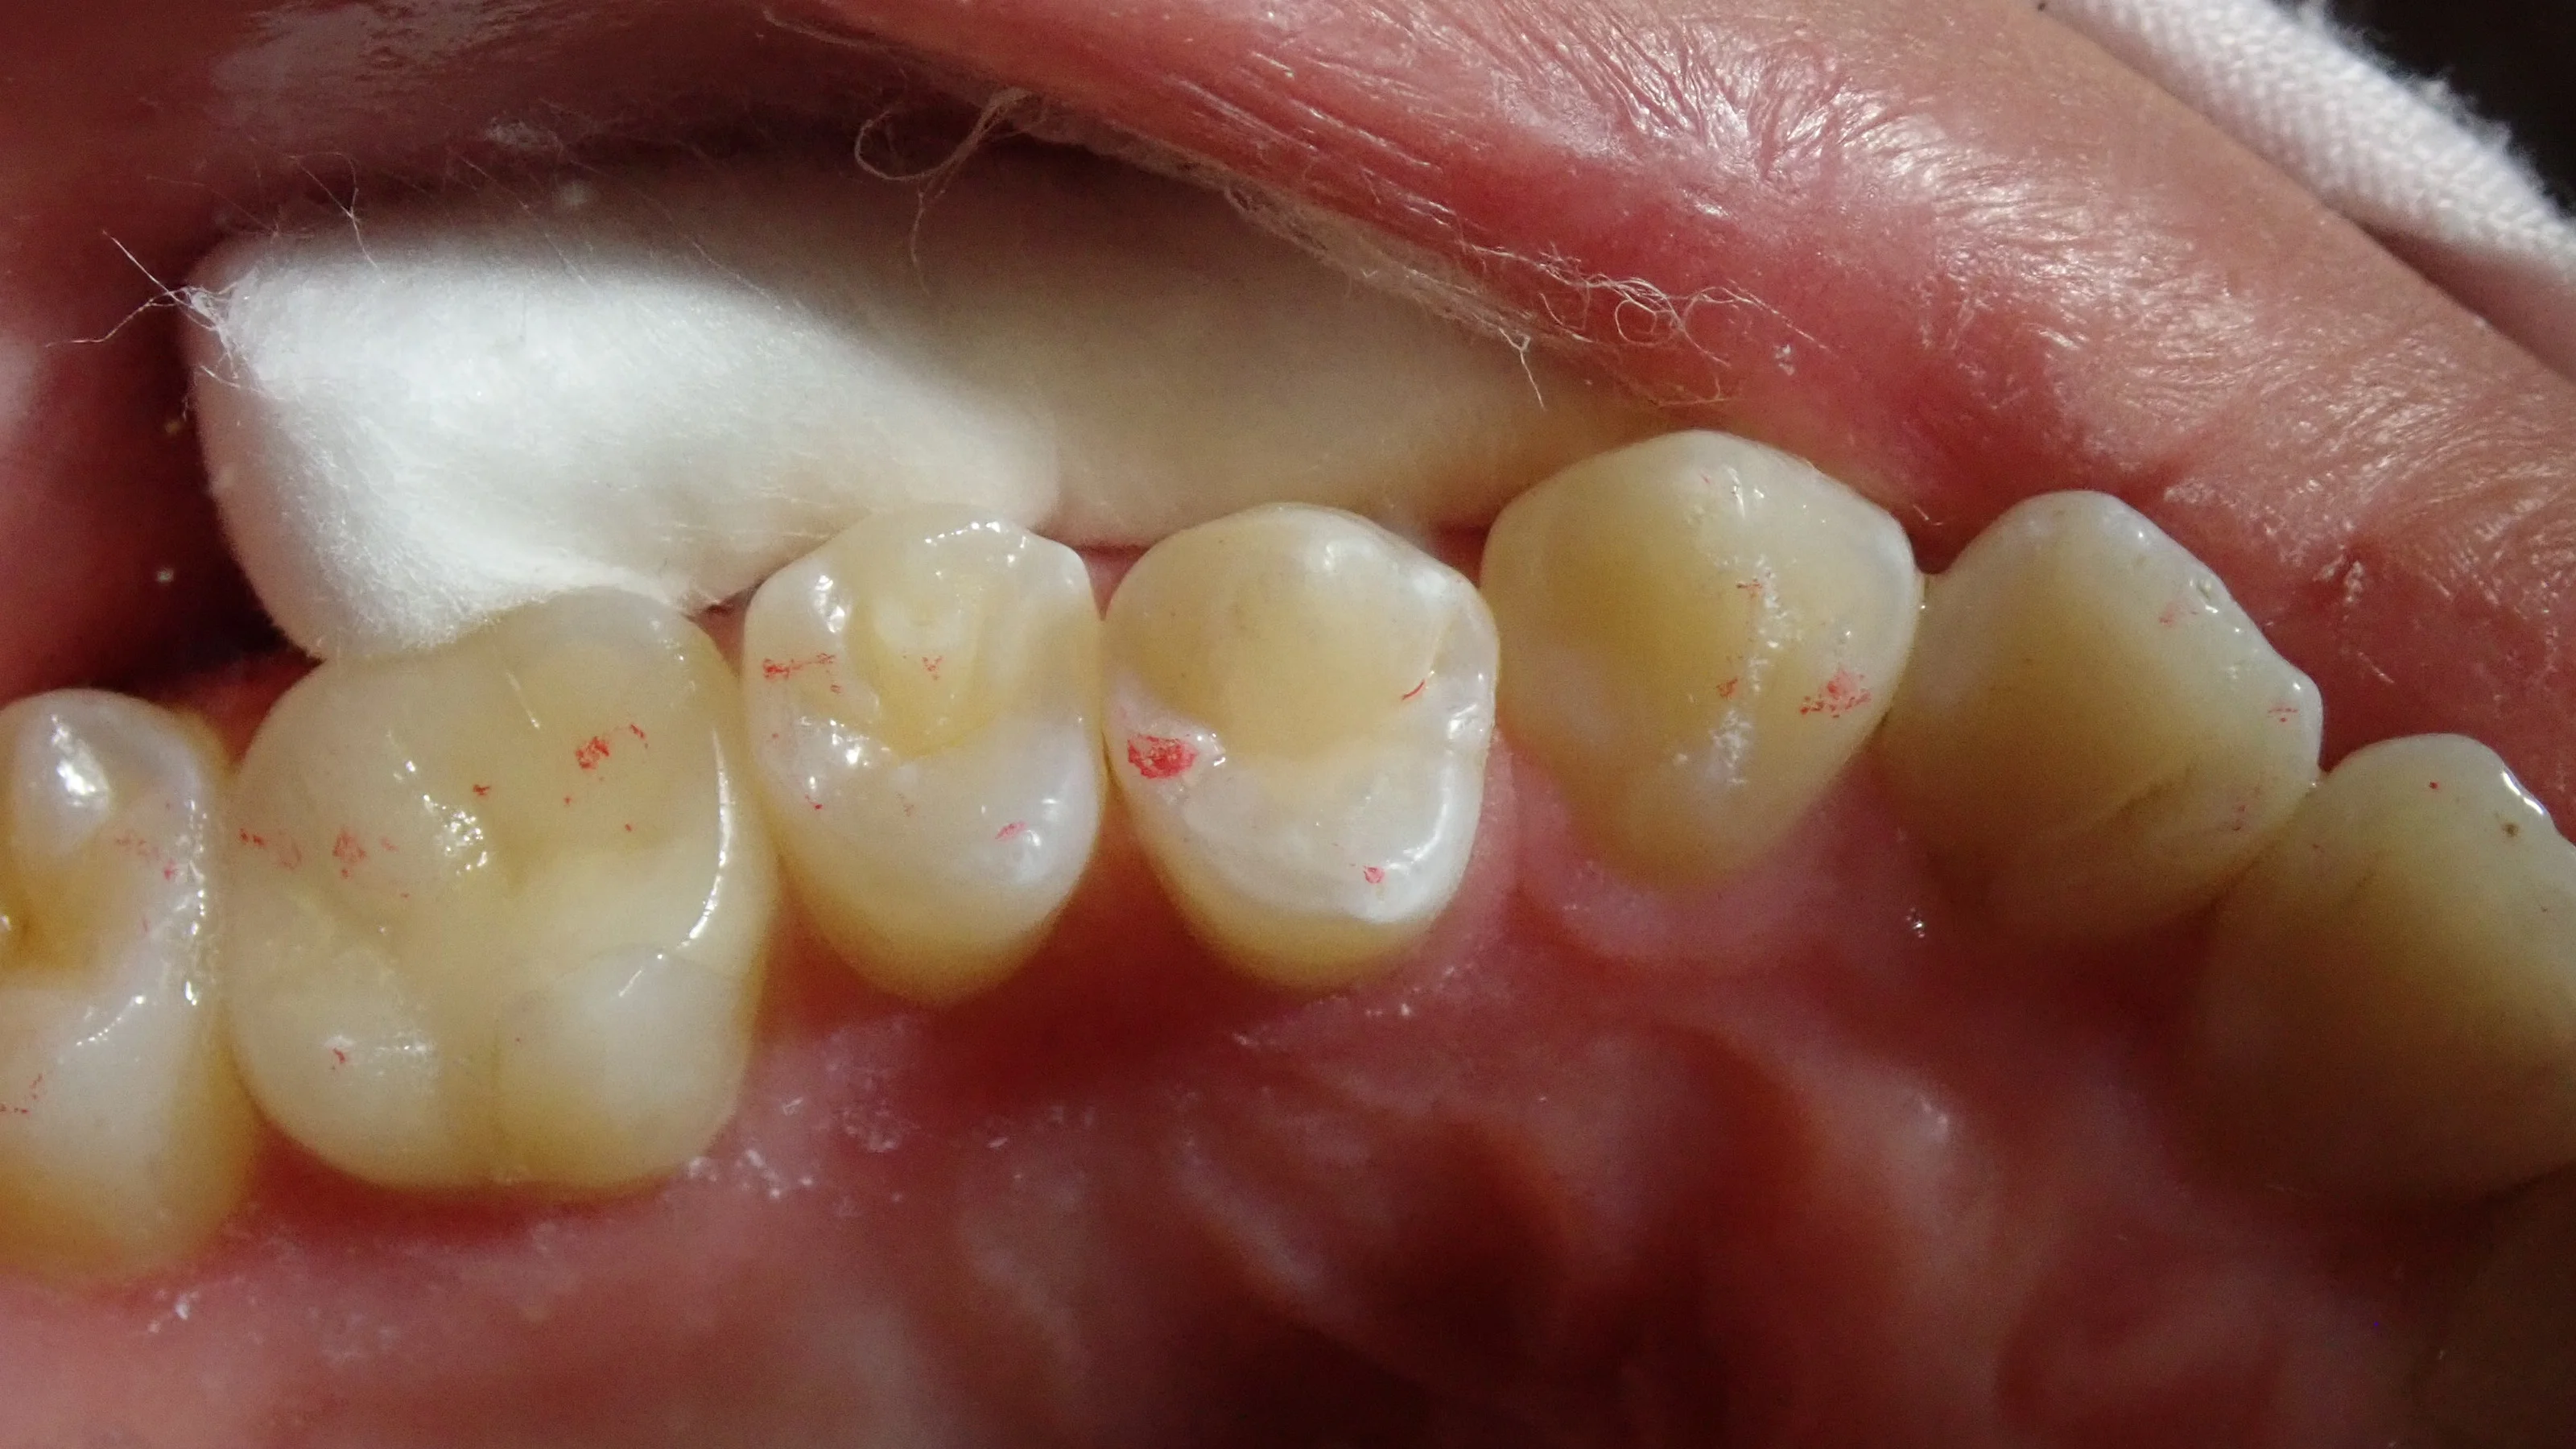

そして、最終的に詰め終わったのがこちら。

色の違いによる段差は少なからず出てしまっていますが、それでも、被せ物などを入れるよりは歯を削る量としても最小で済ませられます。

こんな感じで、小さく詰めた場合はチケットとしては1枚~2枚で済みますが、被せ物となると一気に5~10枚消費するような感じになります。